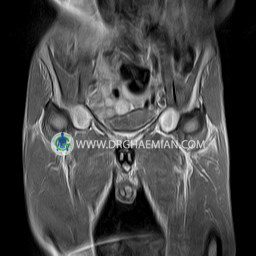

پزشکان اغلب از تصویربرداری ام آر آی برای تشخیص و درمان عارضه های پزشکی که فقط با استفاده از اشعه ایکس یا میدان مغناطیسی و امواج رادیویی قابل مشاهده است، استفاده می کنند. دستگاه ام آر آی تصاویر دقیق از ساختار های داخلی بدن ایجاد می کند. در این کیس استئومیلیت لگن، آتروز و سنیویت دیده می شود.

HIP JOINT MRI

( without contrast )

Technique : coronal STIR , coronal T2 , Axial T1 , axial T2 .

– Heterogeneous signal change (high T2/STIR , low T1) in proximal metaepiphysis of left femur without articular surface irregularity suggestive for bone bruise (stress fracture?), osteomyelitis & arthritis and marrow infiltration (less probable)

– Left hip joint effusion suggestive for synovitis

are seen.

COMMENT: Clinical correlation and MRI with contrast are recommended.